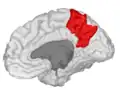

Precuneus of left cerebral hemisphere (shown in red).